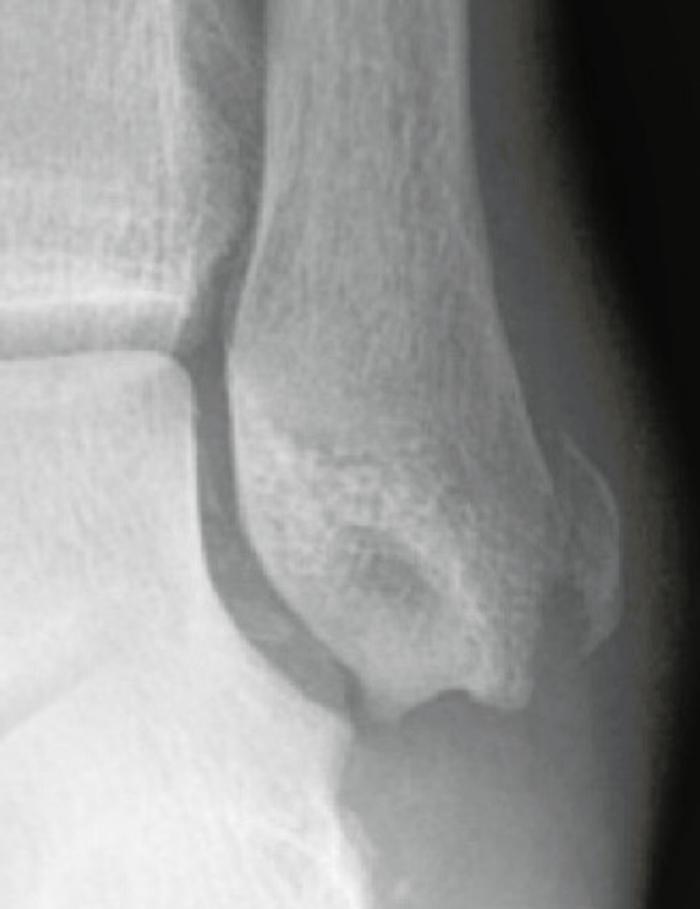

Lateral process of the talus: This is known as the snowboarder’s fracture and is another of the fractures along the lateral border of the foot which may be misdiagnosed as an ankle sprain. It is thought that 40-50% of these fractures can be missed on initial presentation, as the lateral process is very close to the tip of the fibula and the lateral ligaments. The fracture is uncommon, comprising <1% of ankle injuries. The mechanism is thought to be dorsiflexion and inversion of the foot. Careful palpation of the lateral border of the foot will reveal tenderness over the lateral process. The fracture is difficult to diagnose on plain X-rays, because of overlapping bony structures, and an index of suspicion is necessary. A lateral view of the foot, AP mortise view of the ankle and a Broden’s view of the subtalar joint are the best views to show it. Sometimes the degree of pain and swelling may suggest an underlying injury, despite negative X-rays, and a CT is necessary (Figure 5).

Fig 5.jpg

Figure 5: CT showing fracture lateral process talus.

Treatment depends on the size of the fracture, whether it is displaced and whether it involves the joint. Displaced fractures involving the articular surface are best treated with internal fixation. Delayed diagnosis >2 weeks has been associated with poorer outcomes.